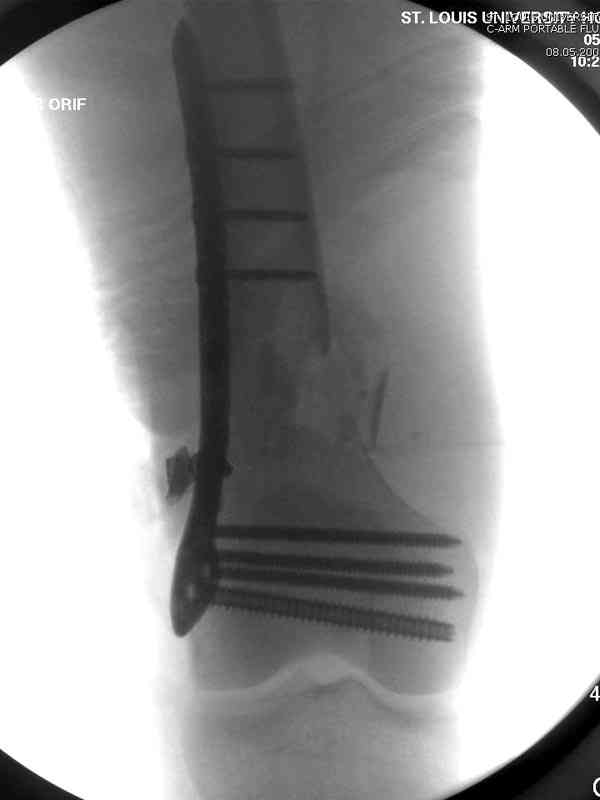

Доступ был латеральный, при вскрытии с задней

поверхности бедра обнаружили кровотечение. Поднятием давления на заранее установленном турникете на конечности проконтролировали кровотечение.

В данном случае мы не ставили осуществление гемостаза приоритетным, после 30 минут больной оставлен вызванному сосудистому хирургу со стабильной фиксацией бедра. Несмотря на выбранный передне-медиальный доступ, хирург произвел восстановление сосудистого повреждения.

Латерально пластину защитили ушиванием

илио-тибиального тракта, а медиальная сторона была ушита мышцей, и все раны закрыли ваккумированием (VAC)

На третий день после Irrigation & Debridment закрыли все раны за исключением компартментальной раны из-за отека, медиально в дефект кости установили Putty Grafton Bone Substitute. На компартментальную рану вакуум и мероприятия по сближению краев раны резиновой стяжкой.

На 9й день с момента травмы ушили рану без натяжения. Больной получает реабилитацию, движения коленного сустава с помощи CPM-continuous passive motion machine. Сегодня выписан.